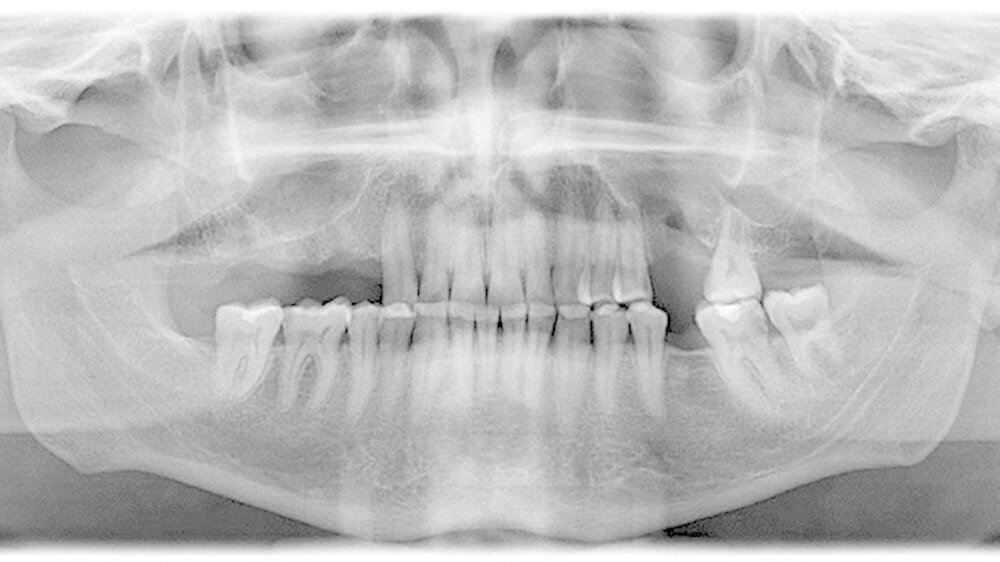

In Intubationsnarkose konnte der Fremdkörper aus dem rechten Sinus maxillaris über einen osteoplastischen offenen Zugang vestibulär regio 014 bis 015 geborgen werden (Abbildung 3). Die Mund-Antrum-Verbindung regio 026 wurde mittels eines Rehrmannlappens verschlossen. Gleichzeitig erfolgte die Entnahme von Proben aus beiden Kieferhöhlen. Die Abbildung 4 zeigt den kunststoffartigen Fremdkörper im Sinne von Füllungsmaterial. Die postoperative Röntgenkontrolle dokumentiert die Entfernung des Fremdkörpers (Abbildung 5) in toto.